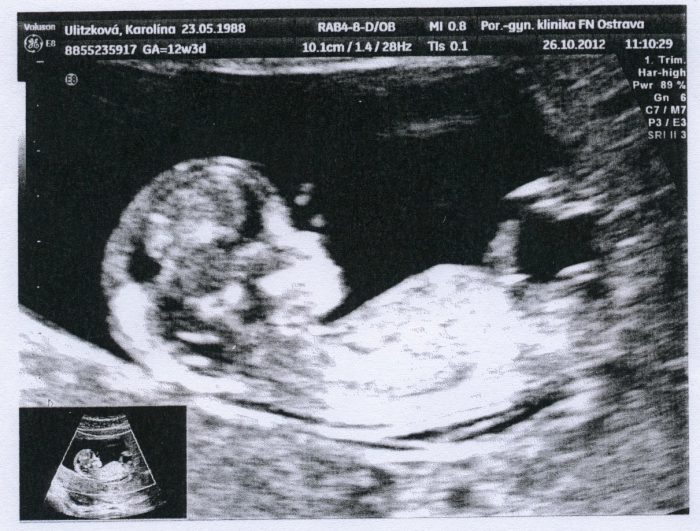

Já se jdu ve středu také jen ujistit zoriazz a hlavně se podívat na to jak už jsme vyrostli. No a konečně si také říci o fotečku, jsem už na konci 1.trimestru a nemám ani jednu fotku